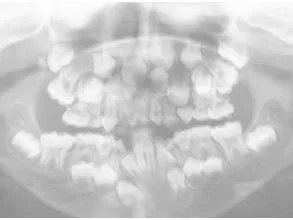

- Alteraciones esqueléticas: En hombros, codos, húmero, caderas, rodillas, columna y caja torácica, dientes…